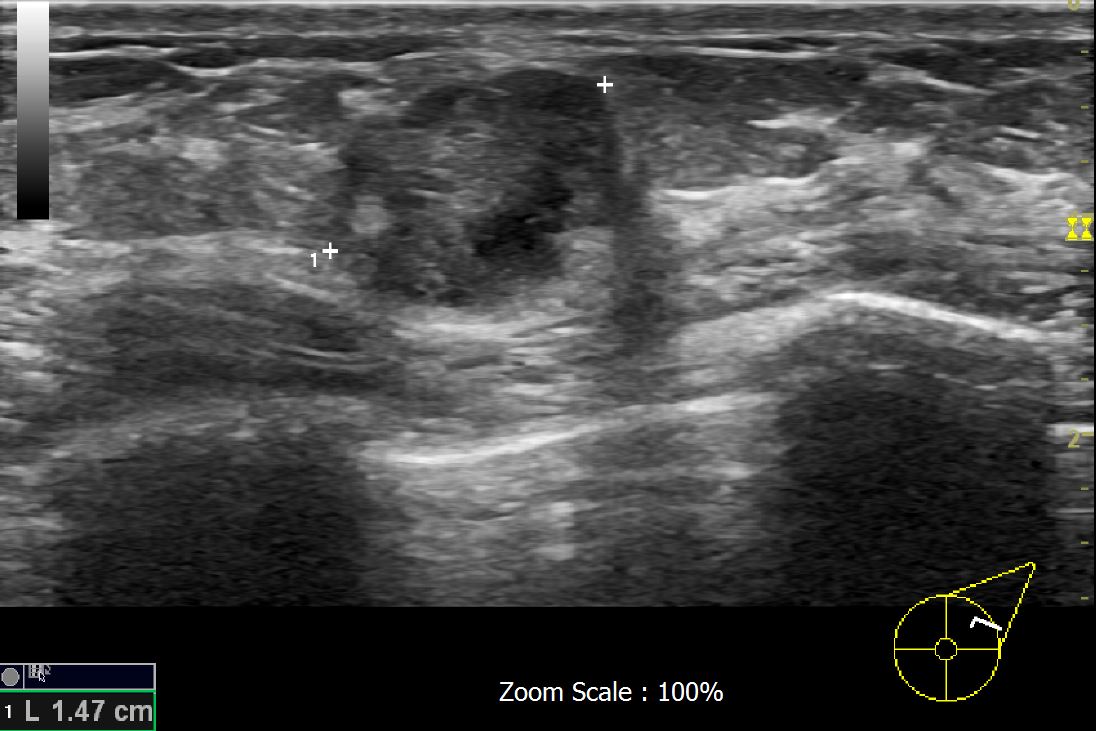

아산 유외과 개원후 619번째 유방암 진단

상기환자 외부검사상이상소견으로 내원하신 60대 여성으로 좌측유방에 의심스러운혹있어 조직검사시행후 유방암진단되었습니다.